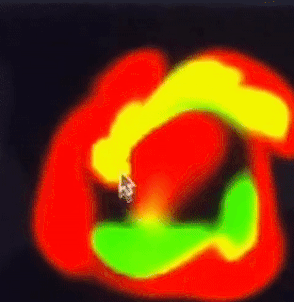

# Jos Stams Fluid